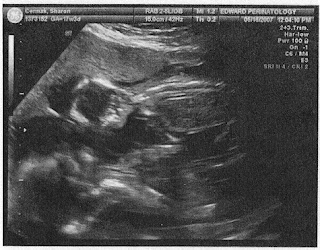

Here's one of them both from June. Looks like they're talking!